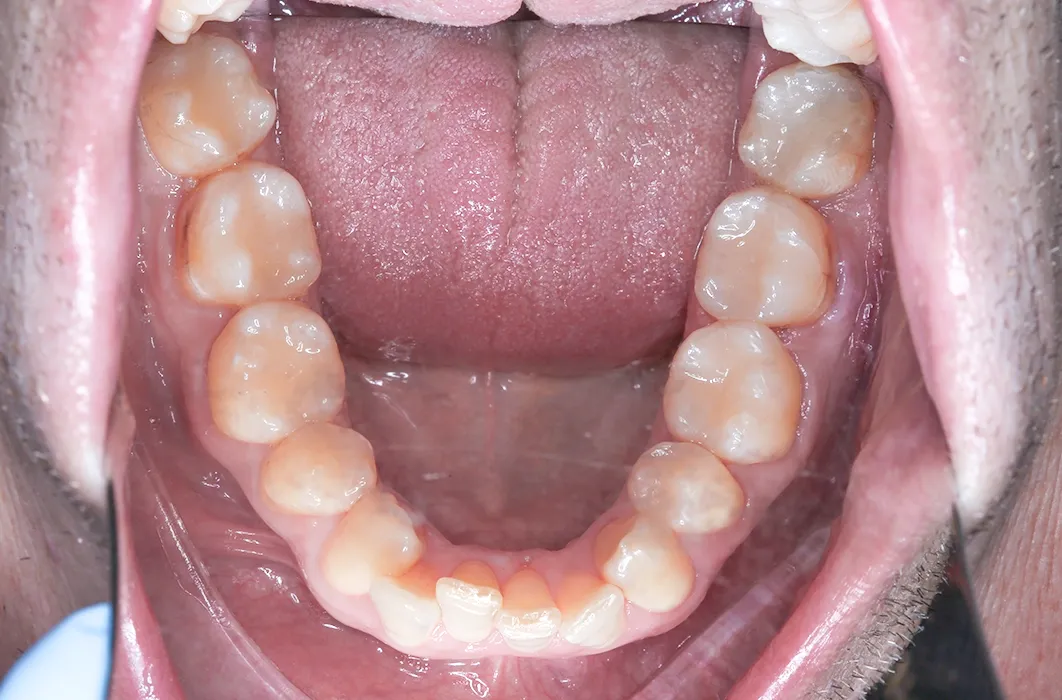

The results

Mr C’s teeth went from being worn, darkened, and at risk of breakdown to looking healthier, stronger, and natural. The resin restorations not only gave his smile a more uniform appearance, but also reinforced surfaces to reduce the risk of future decay and damage.

This case highlights the importance of timely management of worn and decayed teeth. Each patient’s situation is unique, and treatment needs and outcomes will vary, but in this example composite resin fillings were used to:

- Remove areas of decay and replace older amalgam (metal) restorations

- Provide structural support to the affected teeth

- Create a tooth-coloured surface that blends with surrounding teeth

- Maintain the existing teeth in function

In Mr C’s case, composite resin restorations were placed to manage decay and replace older amalgam fillings. This approach provided stability for the affected teeth and maintained them in function.